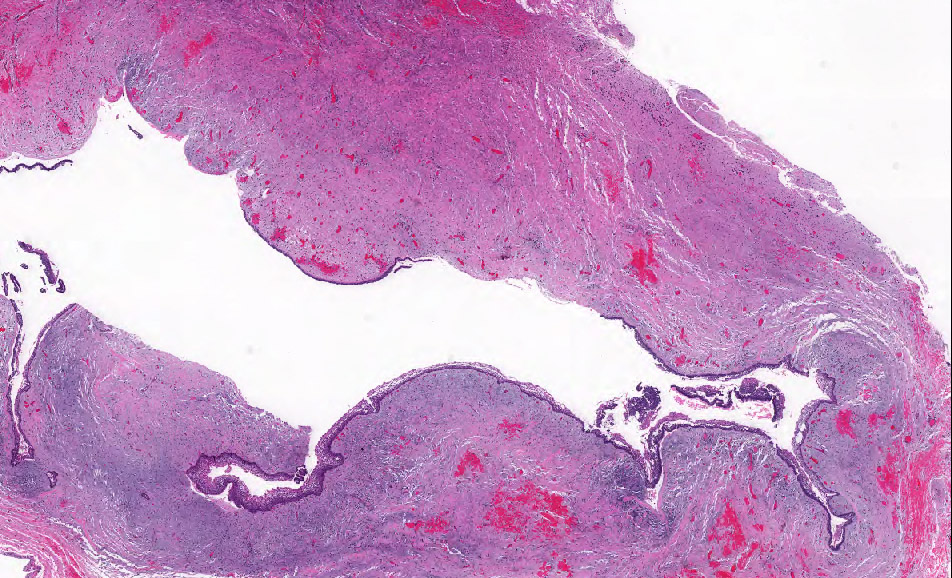

Microscopic (histologic) images

Contributed by Kelly Magliocca, D.D.S., M.P.H. and Anne C. McLean-Holden, D.M.D., M.S.

- Follicular: most common subtype; islands of odontogenic epithelium in fibrous connective tissue; may be cystic; classic peripheral palisading and stellate reticulum-like areas

- Plexiform: cords and sheets of anastomosing odontogenic epithelial cells; classic peripheral palisading and reverse polarity not always obvious

- Ameloblastoma, conventional type has at least 6 histopathological patterns

- Single patterns may predominate within a given lesion, often mixed with 1 or more patterns